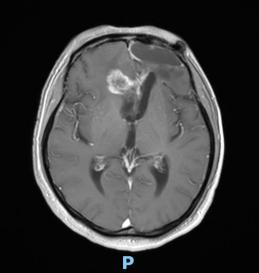

44歲的郭先生(化姓)為膠質(zhì)瘤復(fù)發(fā)患者,復(fù)查發(fā)現(xiàn)顱內(nèi)占位進(jìn)行性進(jìn)展1周,MRI檢查提示瘤體已累積到胼胝體,且瘤體位置較深,手術(shù)難度極高。面對(duì)這一挑戰(zhàn),王虎教授團(tuán)隊(duì)決定采用多種先進(jìn)技術(shù)輔助手術(shù),其中最為引人注目的就是首次引入的細(xì)胞級(jí)顯微鏡EndoSCell?。該設(shè)備是目前全球唯一實(shí)時(shí)在體細(xì)胞級(jí)顯影的儀器,可以輔助醫(yī)生從細(xì)胞層面區(qū)分腫瘤組織與正常組織,從而做到細(xì)胞級(jí)精準(zhǔn)切除。

患者術(shù)前核磁影像

整個(gè)手術(shù)過(guò)程在“腦醫(yī)匯”平臺(tái)進(jìn)行了全程直播,吸引了近千位神經(jīng)外科領(lǐng)域的專家學(xué)者觀看,他們紛紛對(duì)王虎教授團(tuán)隊(duì)的精湛技藝和EndoSCell?的先進(jìn)技術(shù)表示贊賞。術(shù)后,患者的生命體征平穩(wěn),CT及MRI檢查顯示腫瘤切除滿意,無(wú)明顯出血和并發(fā)癥。患者神志清醒,精神狀態(tài)良好,目前恢復(fù)良好。